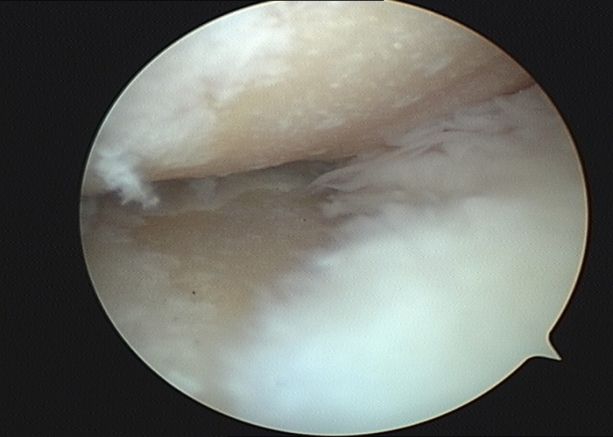

第三階梯:修復性治療。當保守治療無法滿意控制病情時,可考慮微創或矯形手術。①關節鏡清理術:通過微創切口,清除關節內的炎性滑膜、破碎的軟骨和游離體。②截骨術:通過矯正下肢力線,將身體重量從磨損嚴重的一側轉移到相對健康的一側。